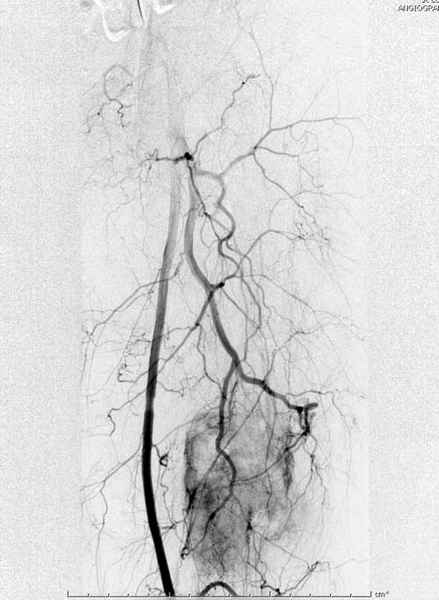

В зависимости от характера опухоли некоторые патологические переломы имеют риск кровотечения во время операции. Множественные литературные данные подтверждают, что надо проявить осторожность при интрамедуллярном остеосинтезе при неизвестных опухолях, особенно где имеется подозрение на Renal Cell Carcinoma. (RCC- hypernephroma) http://www.bonetumor.org/tumors/pages/page64.html

Со слов, больная ничем не болела, только последние 3 месяцев чувствовала боли в бедренной области. КТ брюшной полости подтвердил увеличенную правую почку. (5-6)

Для предупреждения кровотечения во время рассверливания, за день до операции провели эмболизацию сосудов питающий метастаз. http://radiology.rsnajnls.org/cgi/reprint/150/3/673.pdf (7-11, 12-15-16)